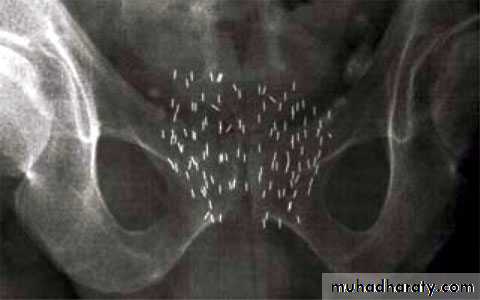

Radiotherapyexternal beam & brachytherapy

Indication:1- Locally advanced disease.

2- Unfit patient for surgery.

3-Symptomatic metastases to relieve pain.

Brachytherapy external beam therapy